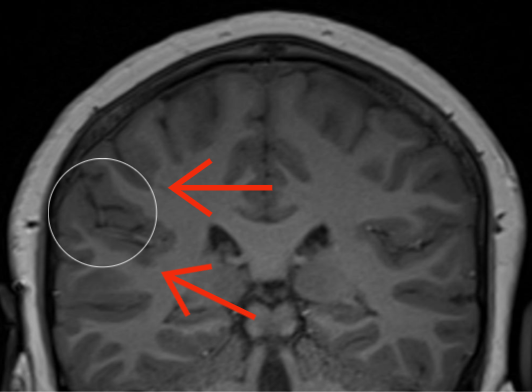

Polymicrogyria (PMG) is a cortical malformation characterized by irregular thickened grey matter in the cerebral cortex, with numerous small gyri, shallow sulci and loss of grey white matter differentiation (see Figure 1). Polymicrogyria is one of the most common malformations of cortical development and is most often related to genetic disorders although it can be caused by congenital viral infection [1]. PMG is a heterogeneous condition which can have variable distribution, extent, and severity [1]. Experienced neuroradiologists can accurately diagnose PMG using magnetic resonance imaging (MRI) but focal or more subtle PMG can be missed. Less experienced readers may not detect PMG with the same accuracy as it can be subtle, and computer aided diagnosis would be useful here.

Figure 1: Difference between PMG and normal brain on coronal T1 weighted MR images. The white circle on the first image shows thickened, irregular grey matter with numerous small gyri and shallow sulci, compared to normal grey matter in the white circle on the second image. The interface between cortical grey matter and white matter is irregular in PMG (red arrows on the first image) and smooth in normal brain (red arrows on the second image).